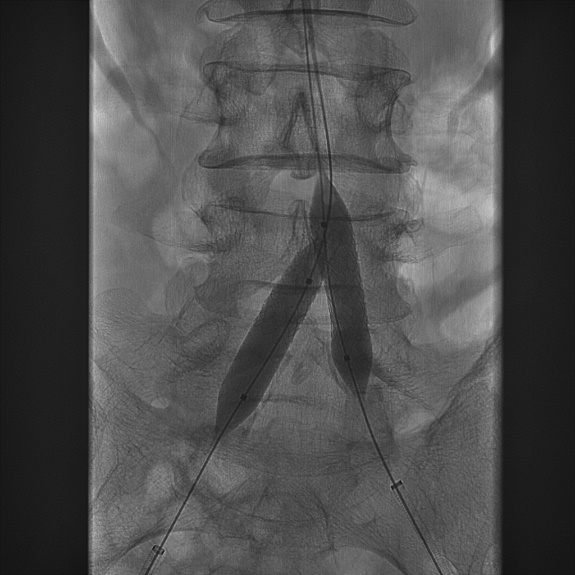

(5) 行双侧髂总动脉“对吻”支架植入术,并双侧导入INVETEC 12*40mm行双侧髂总动脉支架内近端行球囊扩张。

导丝怎么扩【问术ASK】佟铸教授:双侧髂总动脉“对吻”球扩覆膜支架植入术_https://www.jmylbn.com_新闻资讯_第7张

(6) 最后造影示,双侧髂总动脉及远端髂动脉通畅,支架张开充分,贴壁良好,位置理想,无造影及外溢。远端造影未见栓塞。